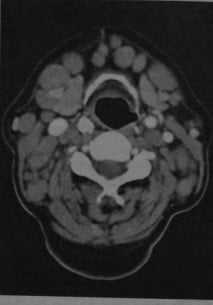

Лимфома шеи у женщины с хроническим лимфолейкозом. КТ с контрастированием: выраженное увеличение размеров и количества шейных лимфатических узлов, особенно в переднем и боковом треугольниках шеи. Плотность лимфатических узлов соответствует окружающим мышцам или выше.